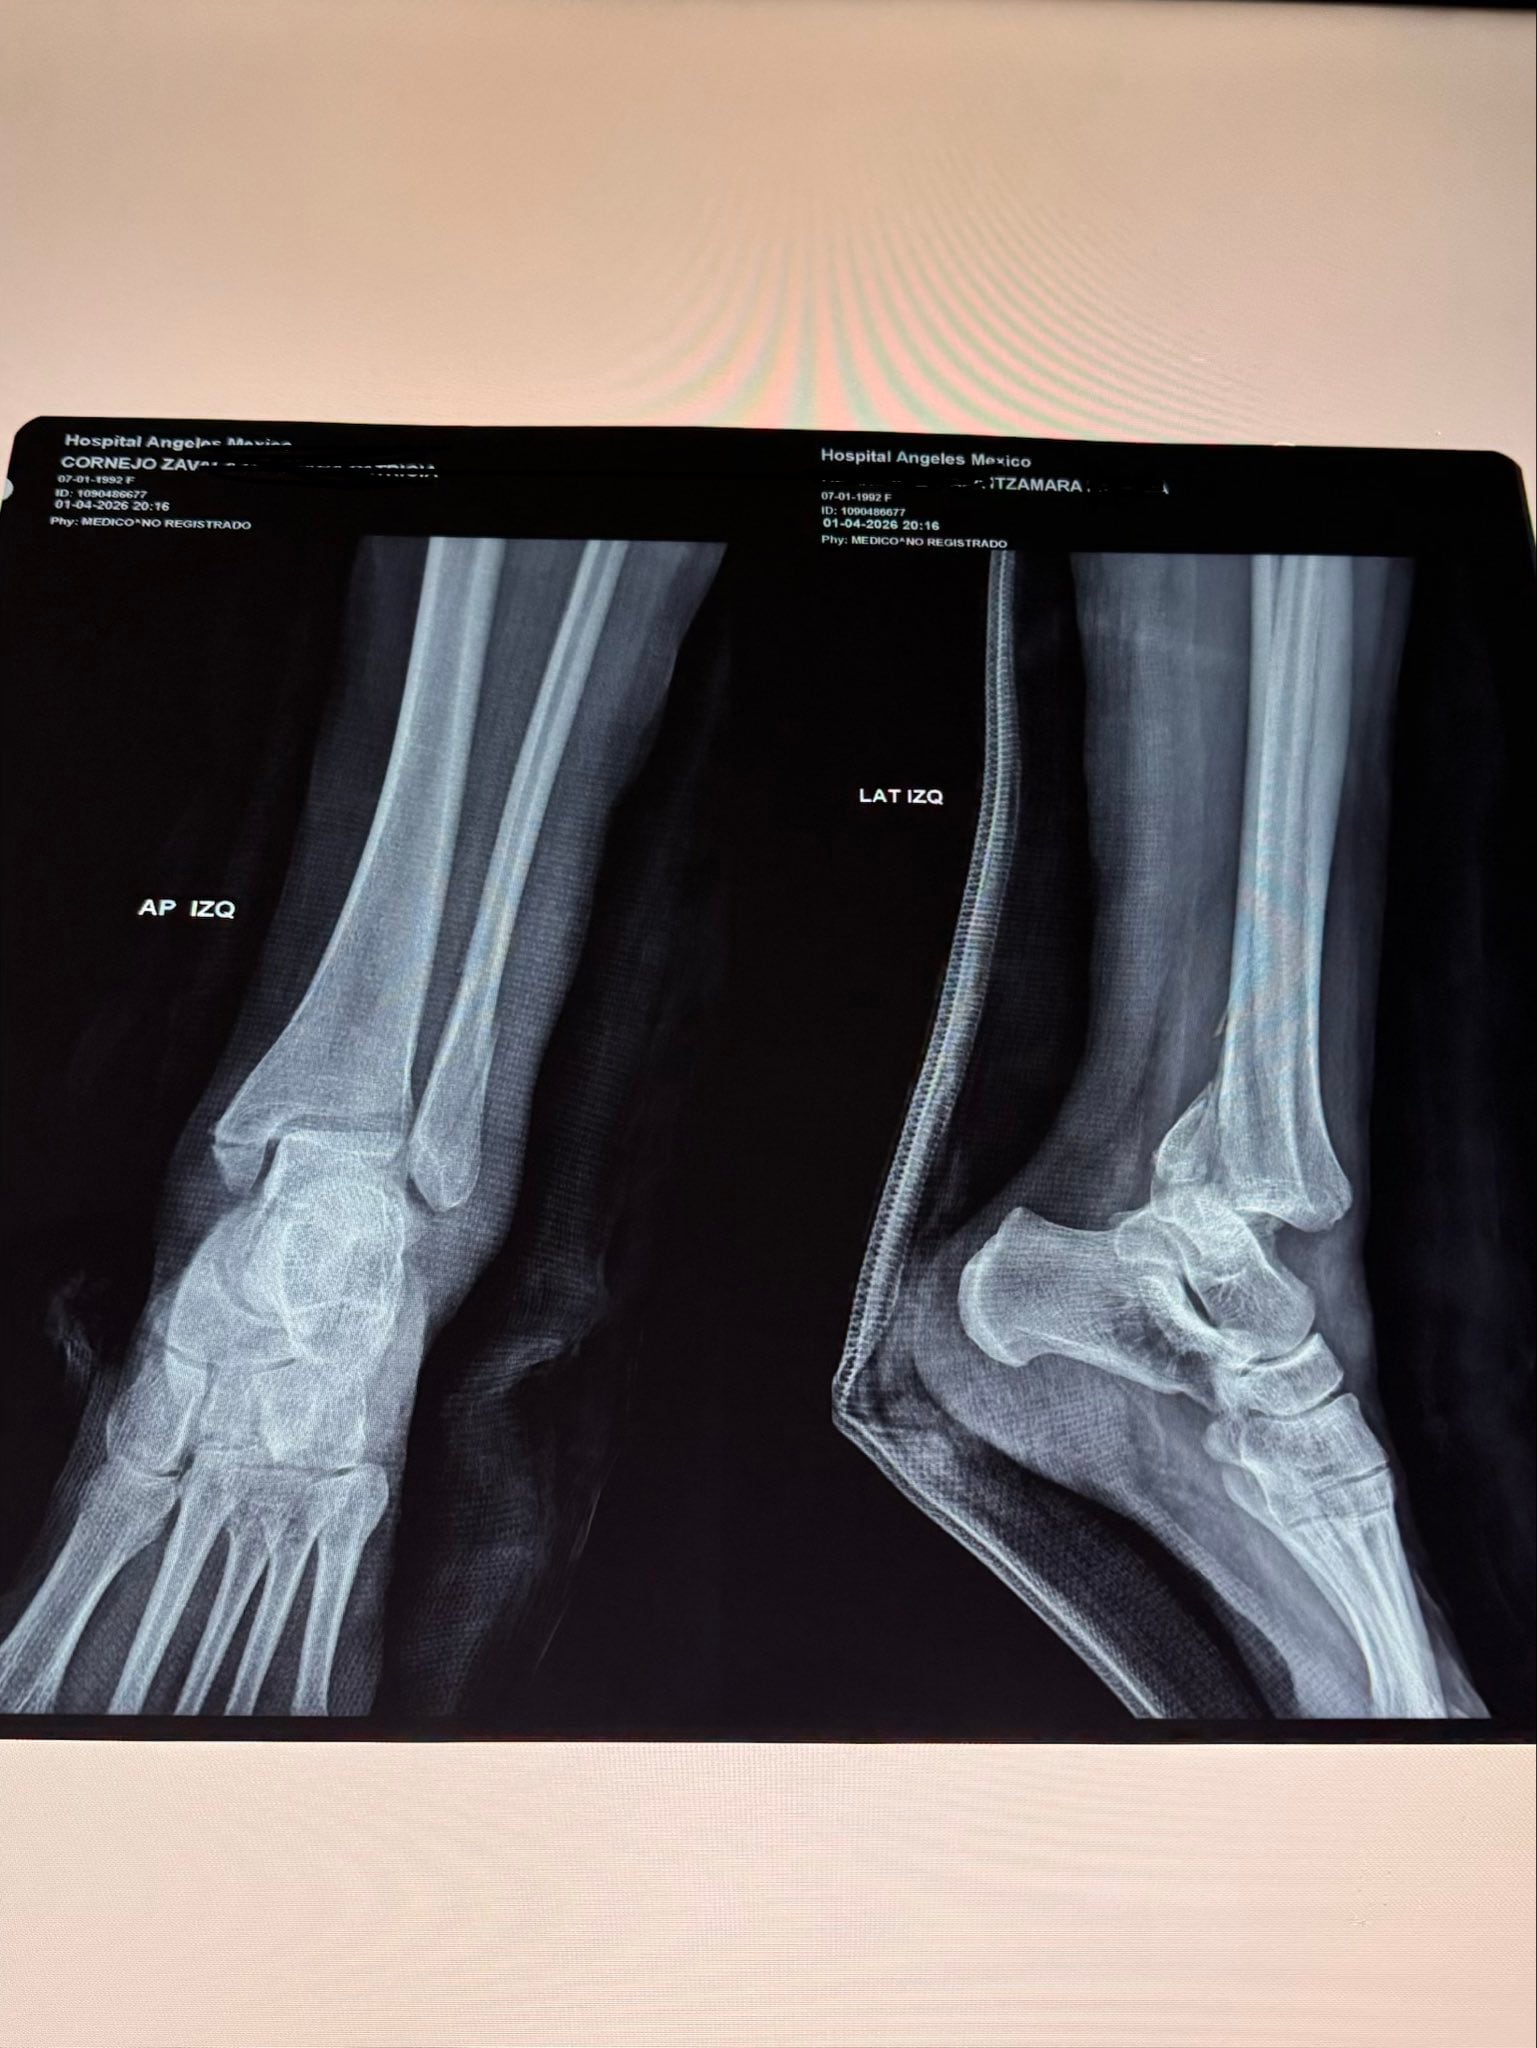

Itzamara compartió que se subió a Jelly World con su bebé de 10 meses, pero al deslizarse por una resbaladilla, terminó con la tibia, peroné y calcaneo fracturados y con una operación donde le colocaron 16 tornillos.

Sin embargo, esto la llevó a una fractura, además de la nula atención de servicio de emergencias que tiene Jelly World y Perisur, pues asegura que los paramédicos fueron tan ineficientes que le dijeron que se había luxado, cuando radiografías demuestran fractura.